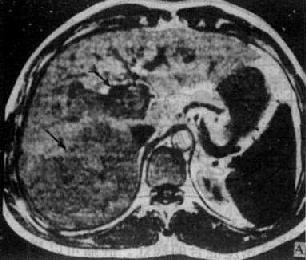

肝血管瘤

图4-3-7 肝血管瘤

CT增强扫描,注射造影剂后10分钟,可见原来两个低密度

区被造影剂基本完全充盈(↓)。图为两个相邻层面